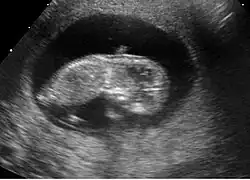

Fœtus à 9 semaines

L'embryon s'appelle désormais fœtus. À cet âge, la fréquence cardiaque du fœtus atteint son maximum à 175 battements par minute.